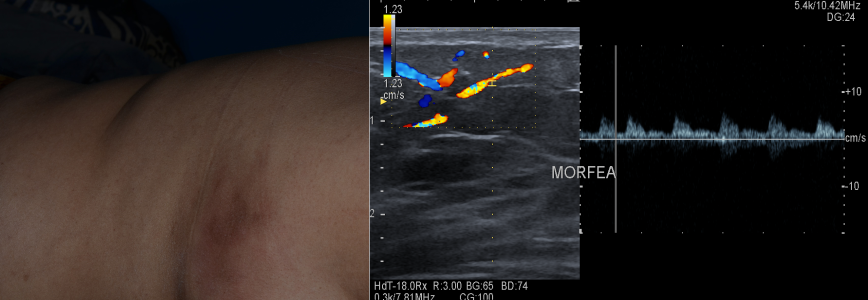

3. MALATTIE AUTOIMMUNI - Sclerodermia cutanea

Morfea: aumento del flusso ematico e dello spessore dermo-idermico